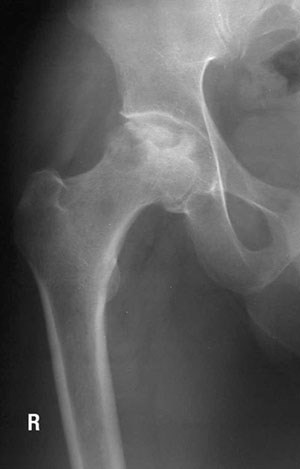

Bone fractures and osteonecrosis have been associated with exposure to common leukemia therapy drugs such as corticosteroids and methotrexate. Bone toxicity is an extremely debilitating condition that often leads to lifelong pain, shortened limbs, has difficult recovery and may lead to impaired quality of life. Our team wanted to explore if there are any genetic variants that make some children more at risk for bone damage including fractures and osteonecrosis.

Our findings are significant, as we found that 20 per cent of the 615 study’s participants had a genetic variant in the gene for thymidylate synthase that was associated with increased risk of bone fractures and osteonecrosis. We also found that kids who were diagnosed with leukemia at age 10 or older were more at risk for bone fractures, while those who were younger than 10 years old when they had leukemia were more at risk for osteonecrosis. This is a novel observation.